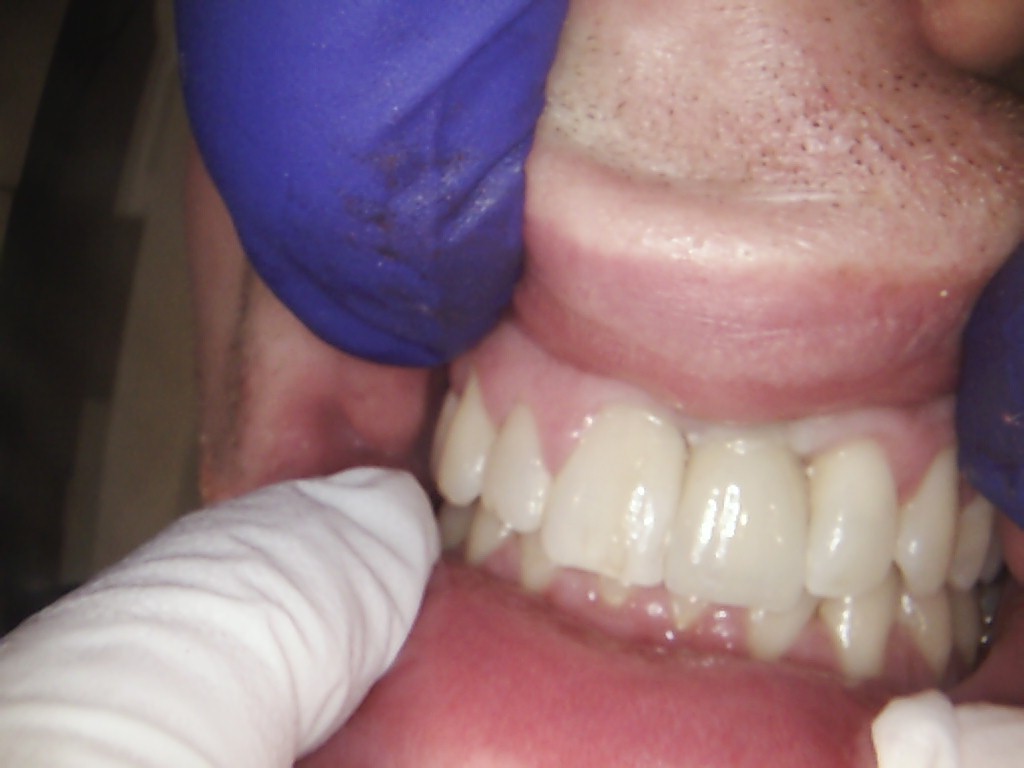

Examples of our work.

Single front tooth case